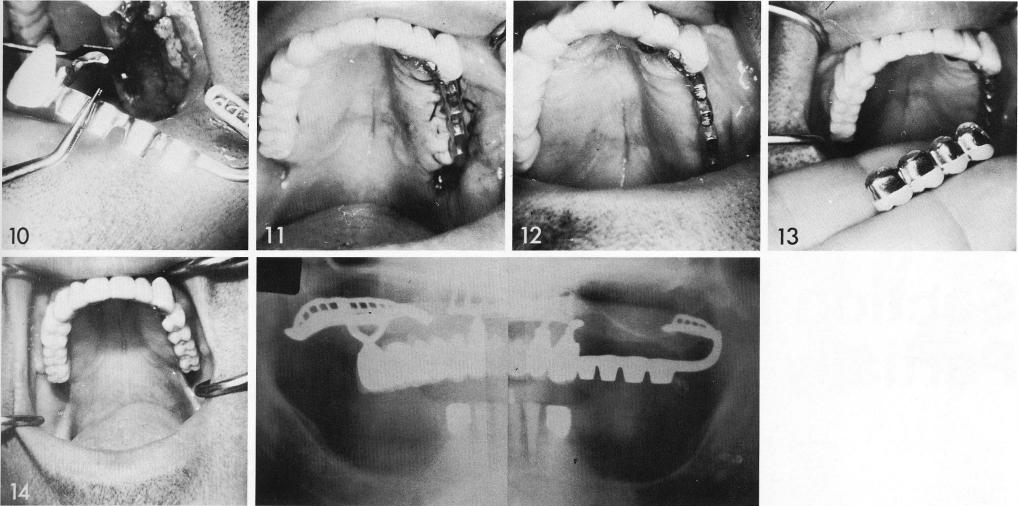

Both a unilateral pterygoid extension implant and a unilateral subperiosteal implant were used for this totally edentulous arch (1). First the subperiosteal implant was executed (2-4), and then the bladevents inserted (5). When the tissues healed (6), the splint was fabricated with an internal screw system (7) for anchoring the pterygoid extension implant. This was positioned (8), and the ridges exposed for the pterygoid extension implant (9,10). After healing (11,12), a four-unit splint completed the restoration (13,14).

1 The maxillary ridges exposed for the pterygoid extension implant